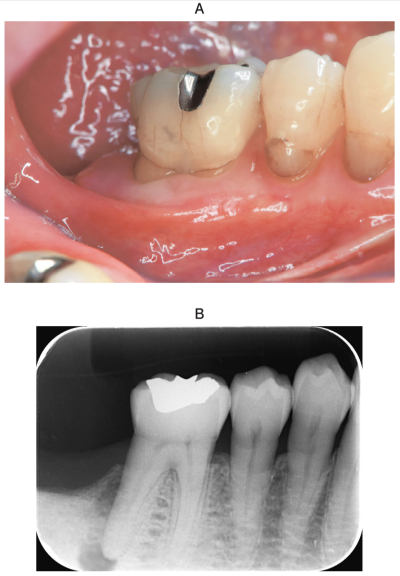

73 歳の男性。下顎右側第一大臼歯の違和感を主訴として来院した。1週前から自発痛があったがそのままにしていたところ、昨日から咬合痛が発現したという。プロービングデプスは遠心で7mm、その他は3mm であった。初診時の口腔内写真とエックス線画像を別に示す。

次に行うべきなのはどれか。1つ選べ。